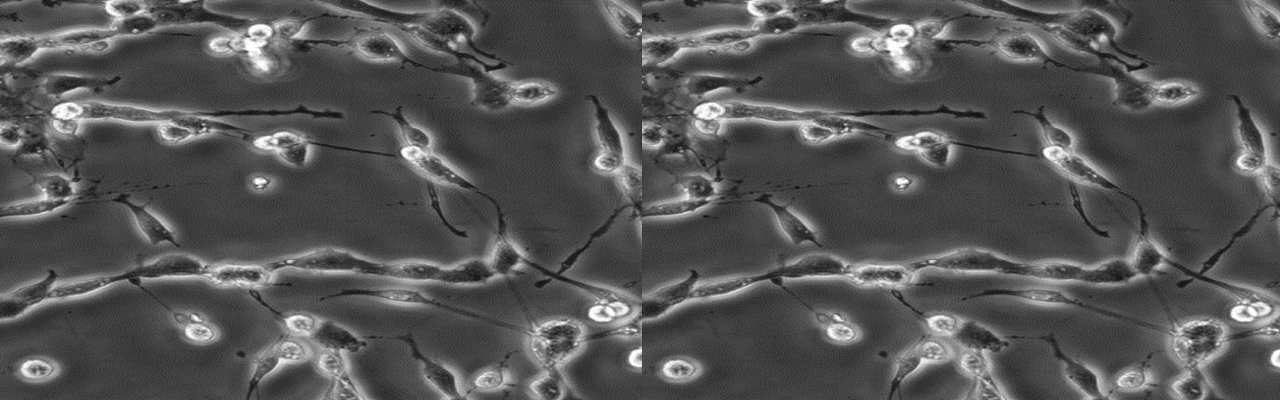

| 细胞全名 | 人神经胶质瘤细胞 |

| 生长特性: | 松散贴壁生长 |

背景资料: H4细胞系建系于1973年。它衍生于一个患神经胶质瘤的37岁病人的脑组织。该细胞的致瘤特性己经被屏蔽,细胞接种动物一般不产生肿瘤结节。该细胞具有修复MNNG损伤5型腺病毒的能力。